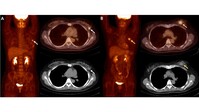

건국대병원, 유방암 재발요인 ‘암대사부피(MTV)’ 지목

건국대병원은 유방암센터 소속 핵의학과 정현우 교수와 외과 노우철 교수가 조기 유방암 환자 재발을 예측할 수 있는 인자로 ‘암대사부피(MTV)’를 지목했다고 6일 밝혔다. 교수팀에 따르면, 암세포는 정상 세포에 비해 포도당을 많이 이용하기 때문에 포도당과 유사한